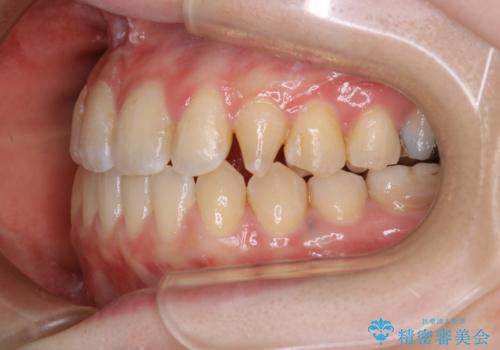

歯科技工士さんの熟練した技術により、周囲の歯としっかりなじむ天然歯のような被せ物をお作りすることが出来ました。

矯正治療と補綴治療をうまく組み合わせることで、美しい口元に仕上げることが出来ました。矯正治療、補綴治療をまとめて行える総合歯科治療を体現した治療といえます。